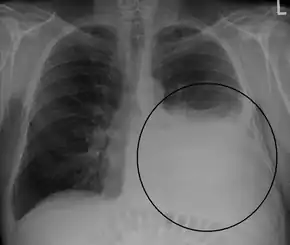

A large left sided pleural effusion as seen on an upright chest X-ray

A pleural effusion is usually diagnosed on the basis of medical history and physical exam, and confirmed by a chest X-ray. Once accumulated fluid is more than 300 mL, there are usually detectable clinical signs, such as decreased movement of the chest on the affected side, dullness to percussion over the fluid, diminished breath sounds on the affected side, decreased vocal resonance and fremitus (though this is an inconsistent and unreliable sign), and pleural friction rub. Above the effusion, where the lung is compressed, there may be bronchial breathing sounds and egophony. A large effusion there may cause tracheal deviation away from the effusion. A systematic review (2009) published as part of the Rational Clinical Examination Series in the Journal of the American Medical Association showed that dullness to conventional percussion was most accurate for diagnosing pleural effusion (summary positive likelihood ratio, 8.7; 95% confidence interval, 2.2–33.8), while the absence of reduced tactile vocal fremitus made pleural effusion less likely (negative likelihood ratio, 0.21; 95% confidence interval, 0.12–0.37).[8]

Imaging

A pleural effusion appears as an area of whiteness on a standard posteroanterior chest X-ray.[9] Normally, the space between the visceral pleura and the parietal pleura cannot be seen. A pleural effusion infiltrates the space between these layers. Because the pleural effusion has a density similar to water, it can be seen on radiographs. Since the effusion has greater density than the rest of the lung, it gravitates towards the lower portions of the pleural cavity. The pleural effusion behaves according to basic fluid dynamics, conforming to the shape of pleural space, which is determined by the lung and chest wall. If the pleural space contains both air and fluid, then an air-fluid level that is horizontal will be present, instead of conforming to the lung space.[10] Chest radiographs in the lateral decubitus position (with the patient lying on the side of the pleural effusion) are more sensitive and can detect as little as 50 mL of fluid. At least 300 mL of fluid must be present before upright chest X-rays can detect a pleural effusion (e.g., blunted costophrenic angles).